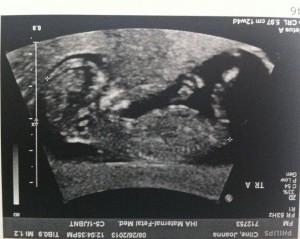

Good morning! I’m 10w1d today and we went for another ultrasound this morning. The u/s tech told us that everything looks exactly as she’d want it to at this point in the pregnancy. The heartbeats are great and they are wiggling around in there!

I’ve attached a few new photos – close ups of each and one group shot. 🙂